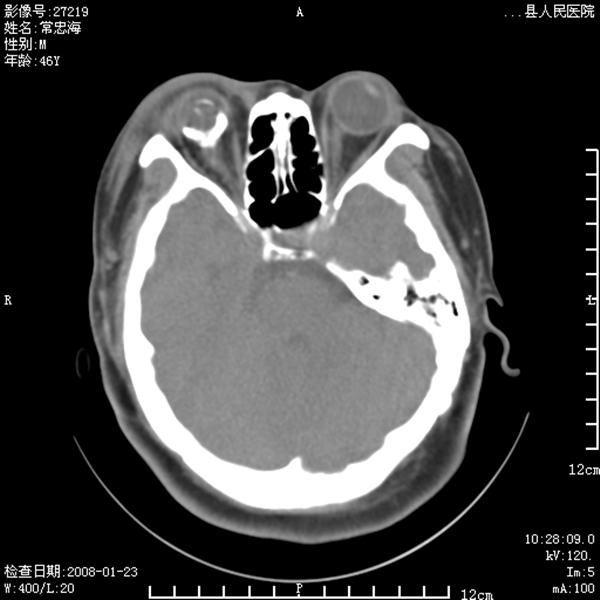

以下是引用江边学者在2008-4-19 22:26:00的发言:[br]1.胼胝体发育不良。[br]2.右侧眼球痨。[br]3.右侧颜面部软组织挫伤。